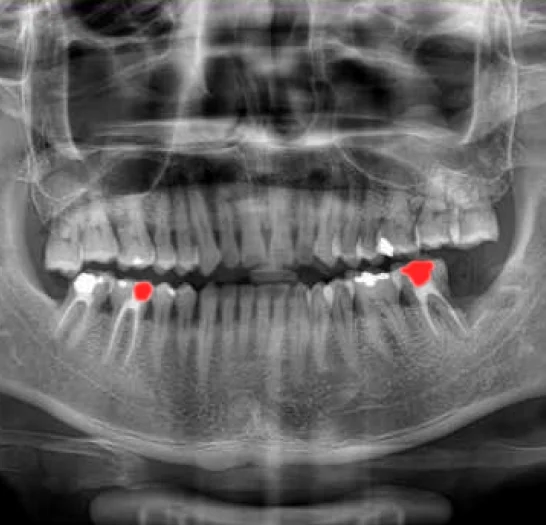

Orthopantomogram (OPG) Annotation & Segmentation

Our annotation services for panoramic dental X-rays provide a comprehensive view of the entire mouth, including upper and lower jaws, teeth, temporomandibular joints (TMJ), and surrounding bone structures. We carefully identify and label cavities, root canals, cystic lesions, bone loss from periodontal disease, fractures, and impacted teeth. These detailed annotations allow AI models to deliver thorough oral health assessments, detect dental issues, and support effective treatment planning.